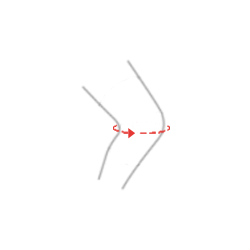

Как в случае легких, так и серьезных травм врач порекомендует отдых с разгрузкой и иммобилизацией коленного сустава. Для этой цели идеально подходит детский ортез AM-DOSK-O/1R имеющий шарнир с диапазоном регулировки подвижности сустава с шагом в 15°.

Характеристика изделия

Детский ортез открытого типа AM-DOSK-O/1R прекрасное решения для иммобилизации и боковой стабилизации колена. Ортез имеет инновационный шарнир с возможностью установки угла сгибания и разгибания колена каждые 15°, обеспечивающий при необходимости ограниченную подвижность или полную иммобилизацию сустава.

Наш детский ортез колена AM-DOSK-O/1R отлично стабилизирует коленный сустав во фронтальной плоскости, обеспечивая его стабилизацию даже в случае высокой нестабильности. В случае травмы колена при кручении и необходимости обездвиживания сустава, ортез позволяет устанавливать часы под углом 0°. Однако в процессе лечения и увеличения диапазона подвижности шарниры ортеза позволяют установить желаемый угол изгиба.